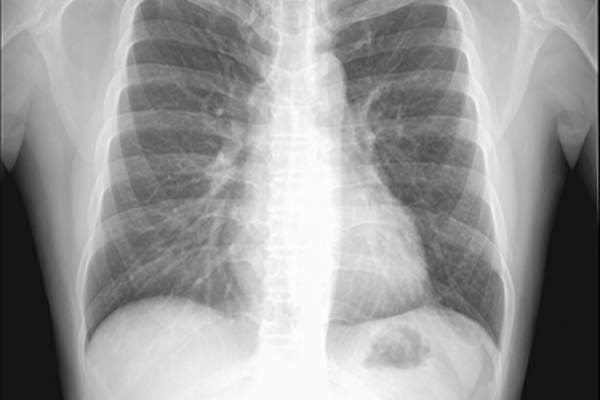

CT扫描

也被称为CAT扫描或计算机断层扫描,这一系列的x射线被用来提供你肺部的详细视图,包括任何可疑的肿块。对于那些潜在的非小细胞肺癌患者,胸部CT扫描通常覆盖肝脏、肾上腺和肺,不仅用于确定肿瘤或肿瘤的位置,还用于确定附近淋巴结是否存在癌症。